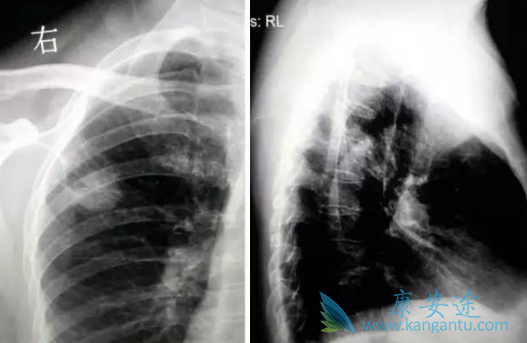

在治疗肺癌的过程中,早期可以通过手术的方式治疗,但是等到晚期,靶向药印度易瑞沙(GEFINAT)成为肺癌的救命稻草,那印度易瑞沙见效后需要吃多久?服用期间副作用大吗?印度易瑞沙一般在口服1至2周左右就开始见效,一个治疗药物有效的话,从国内国外临床研究中,没有证据表明还可以停药的,目前来看靶向治疗是有效的治疗手段,就应该服用下去。

从另外一个角度,一个癌症病人,特别是肺癌的病人,还用五年生存率计算人的生存时间三年五年,希望真正活十年、二十年,一直吃易瑞沙(GEFINAT)能活下去,不是更好。靶向治疗是持续治疗下去,不是吃多长时间,停多长时间。作为能够大大提高晚期肺癌患者生存质量和生存期的靶向药,易瑞沙效果好副作用大吗?